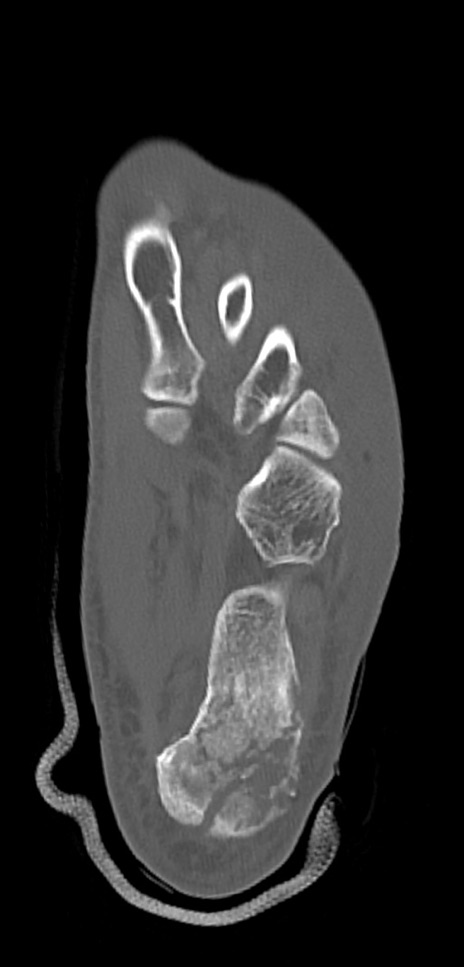

左足関節CT

冠状断像